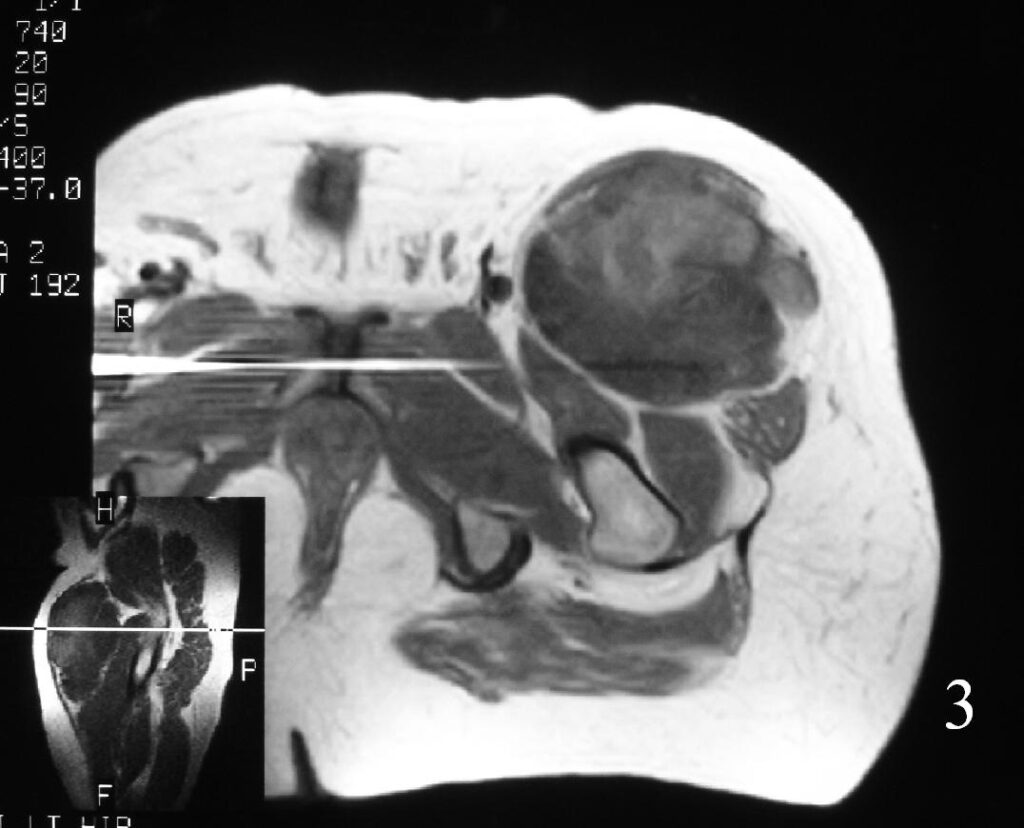

MRI (Fig. 3-7)

• Shows lobulated soft tissue mass

• Signal intensity similar to that of skeletal muscle on T1W

• Heterogenous signal intensity greater than that of fat on T2W

Fig. 3

Fig. 4

Fig. 3-7 Axial MRI of the lower extremity shows an extraskeletal soft tissue chondrosarcoma in different sequences with and without contrast (Fig. 3, 4, 5). Sagittal MRI (Fig. 6, 7) T1 with-without contrast demonstrates enhancement of the mass